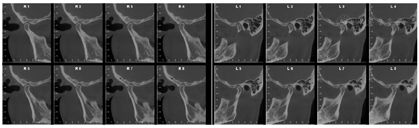

X线示37区于就诊前外院植入种植体(位置较差),15、16种植体联冠,全口牙牙槽骨吸收至根尖1/2~根尖1/3,尤以11、22、32牙槽骨吸收为甚。双侧颞下颌关节区骨皮质连续,形态不完全对称。安氏Ⅱ类+骨性Ⅱ类;低角水平生长型;牙周炎(重度);牙列拥挤合并牙列散隙及三角间隙;深覆盖Ⅲ°;

(1)正面观面上1/3比例稍短,面下1/3高度正常;颏部右偏2 mm;上下颌牙齿中线与面中线不一致;上颌中线右偏3 mm;下颌中线右偏2 mm;侧貌突;双侧颞下颌关节区无压痛及弹响,开口度及开口型未见异常;11、21根尖区瘘管;右侧尖牙、磨牙关系远中关系,左侧尖牙、磨牙远中关系;覆盖Ⅲ°,覆合Ⅰ°;上前牙牙轴均向右侧倾斜,15、16联冠,上颌间隙6 mm,37牙列缺失,下颌拥挤度3.5 mm(图1,图2)。(2)牙周会诊检查:口腔卫生欠佳,菌斑指数PLI:2~3,牙石(++~+++),色素(+~++)。全口牙龈色暗红,牙龈厚钝,质地松软,牙龈无剥削。探诊深度PD>3 mm,附着丧失AL+,牙龈出血指数BI:2~4,BOP(+)。根分叉病变FI:Ⅱ,11、22松动Ⅲ°,23松动Ⅱ°,12、36~41松动Ⅰ°(图3)。